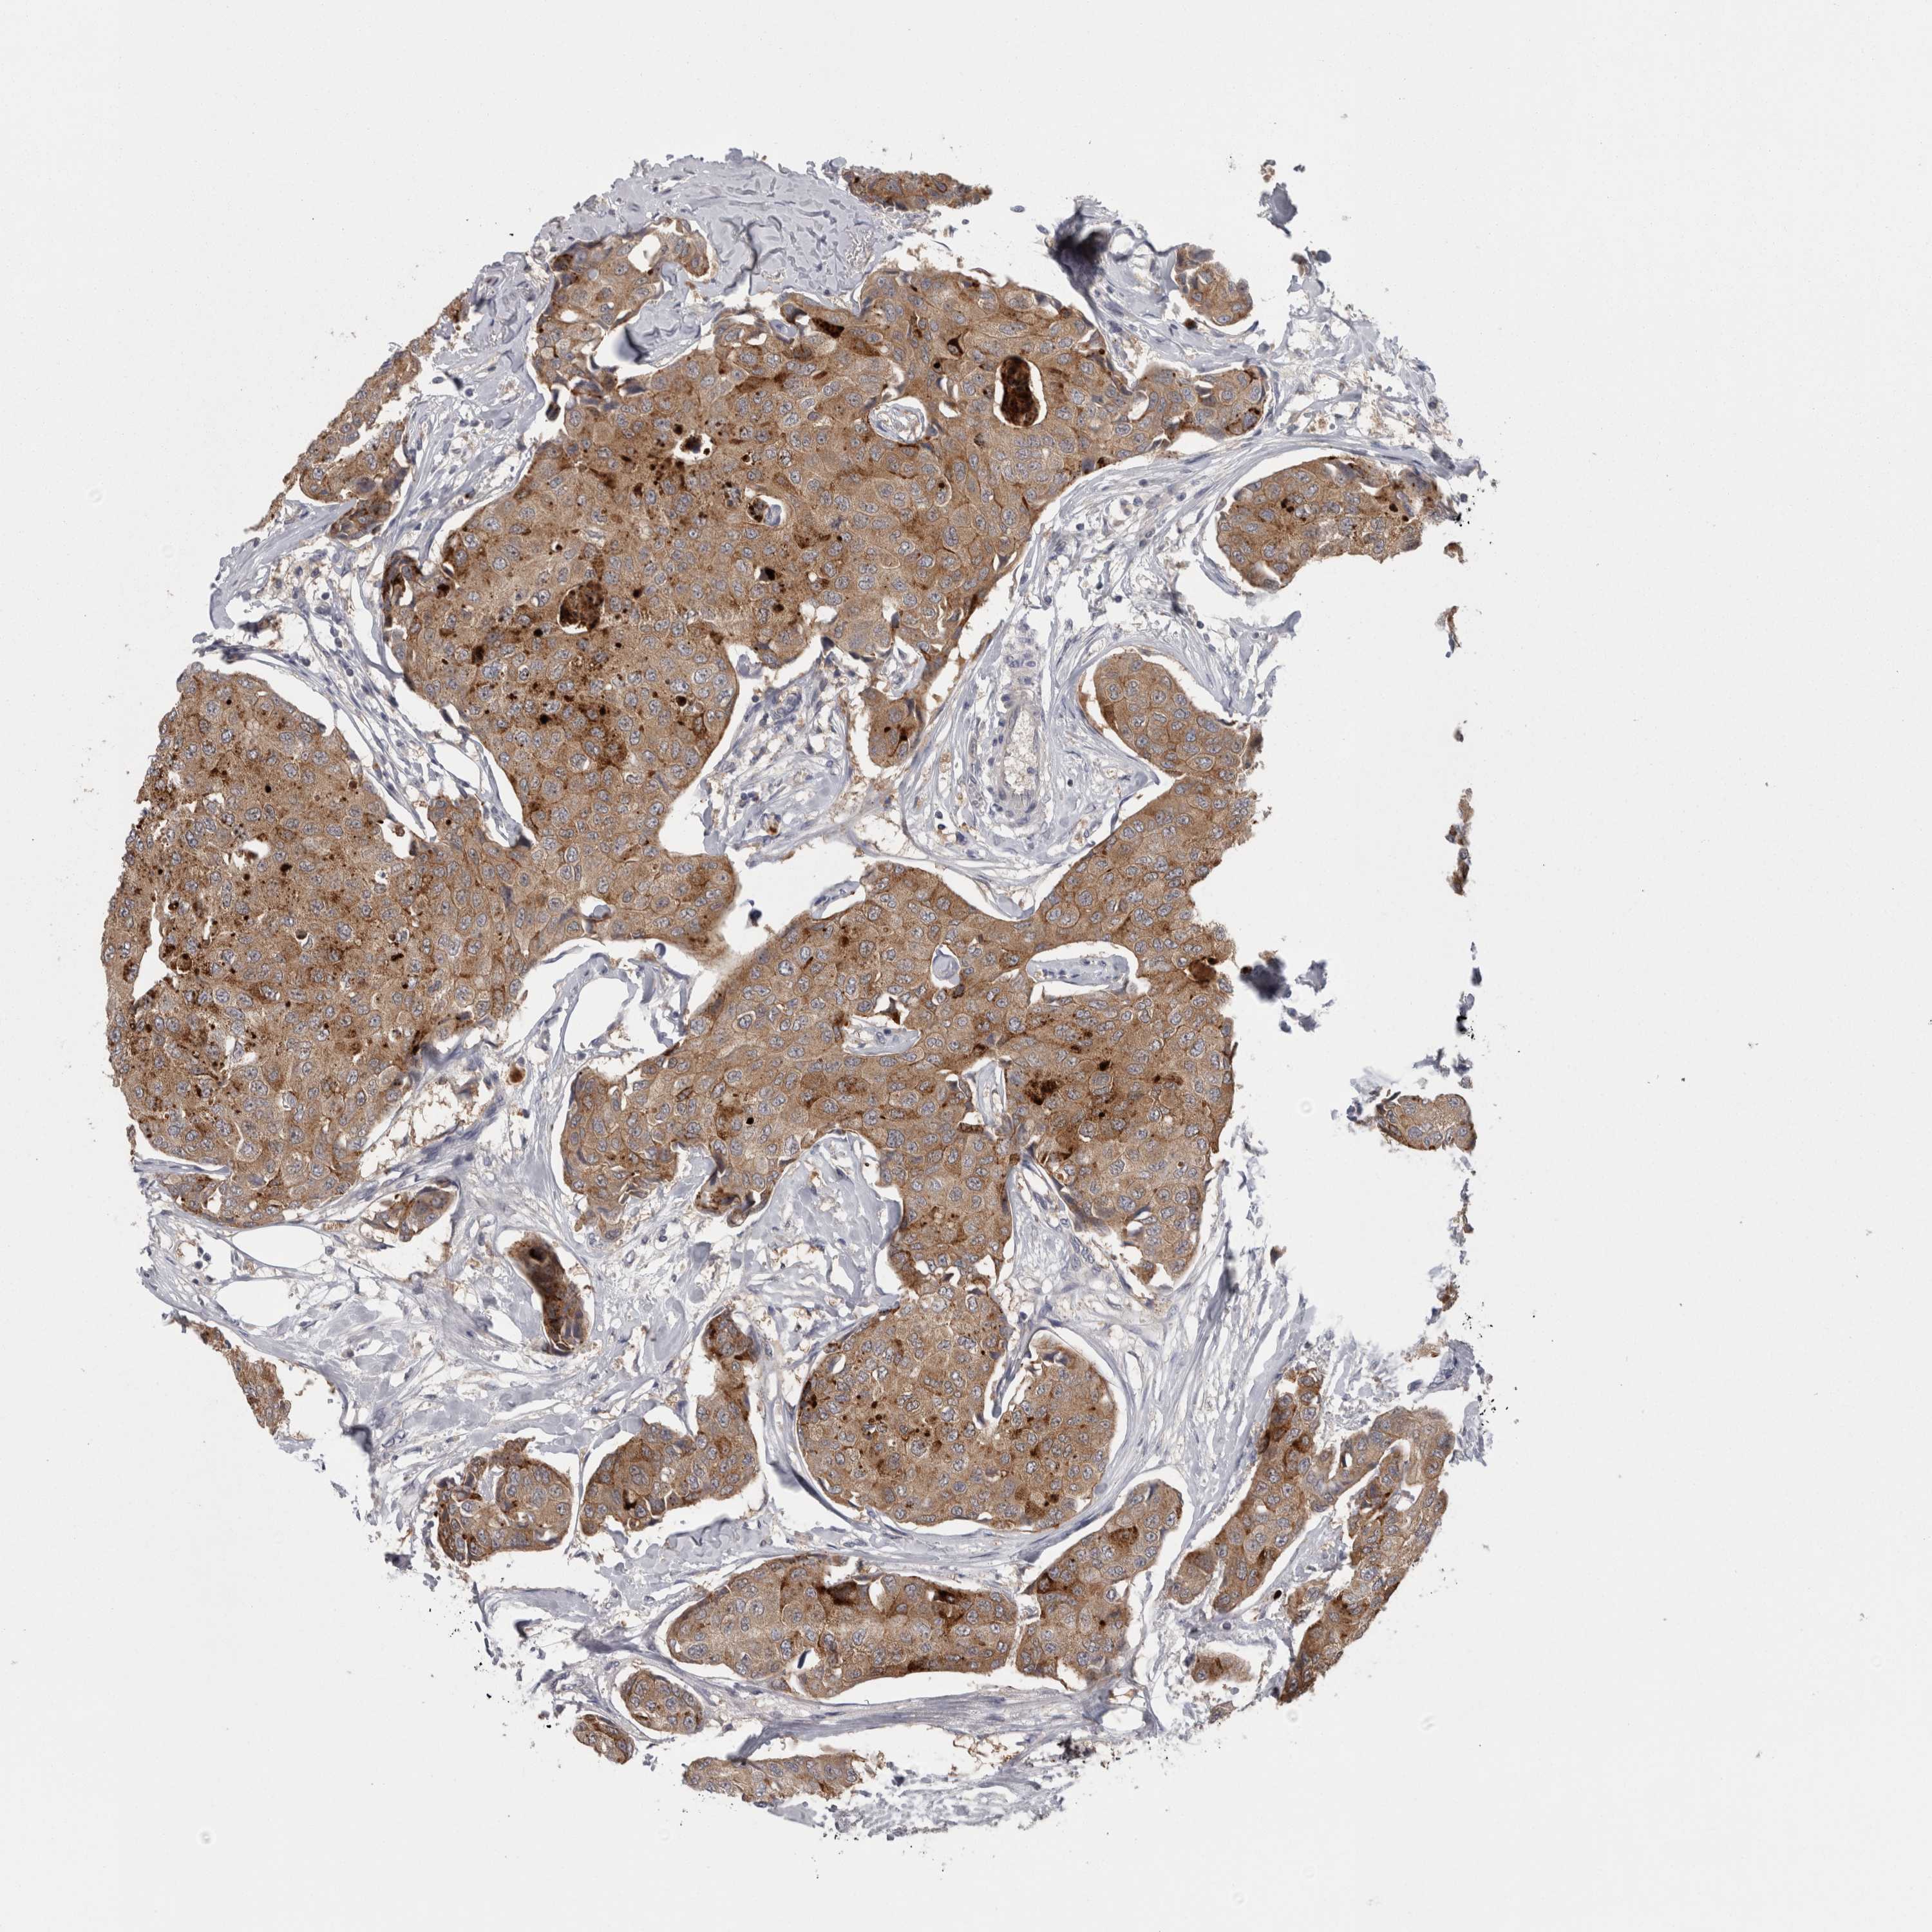

CANCER BREAST CANCER Show tissue menu

BRCA TCGA BRCA VALIDATION PROTEIN EXPRESSION